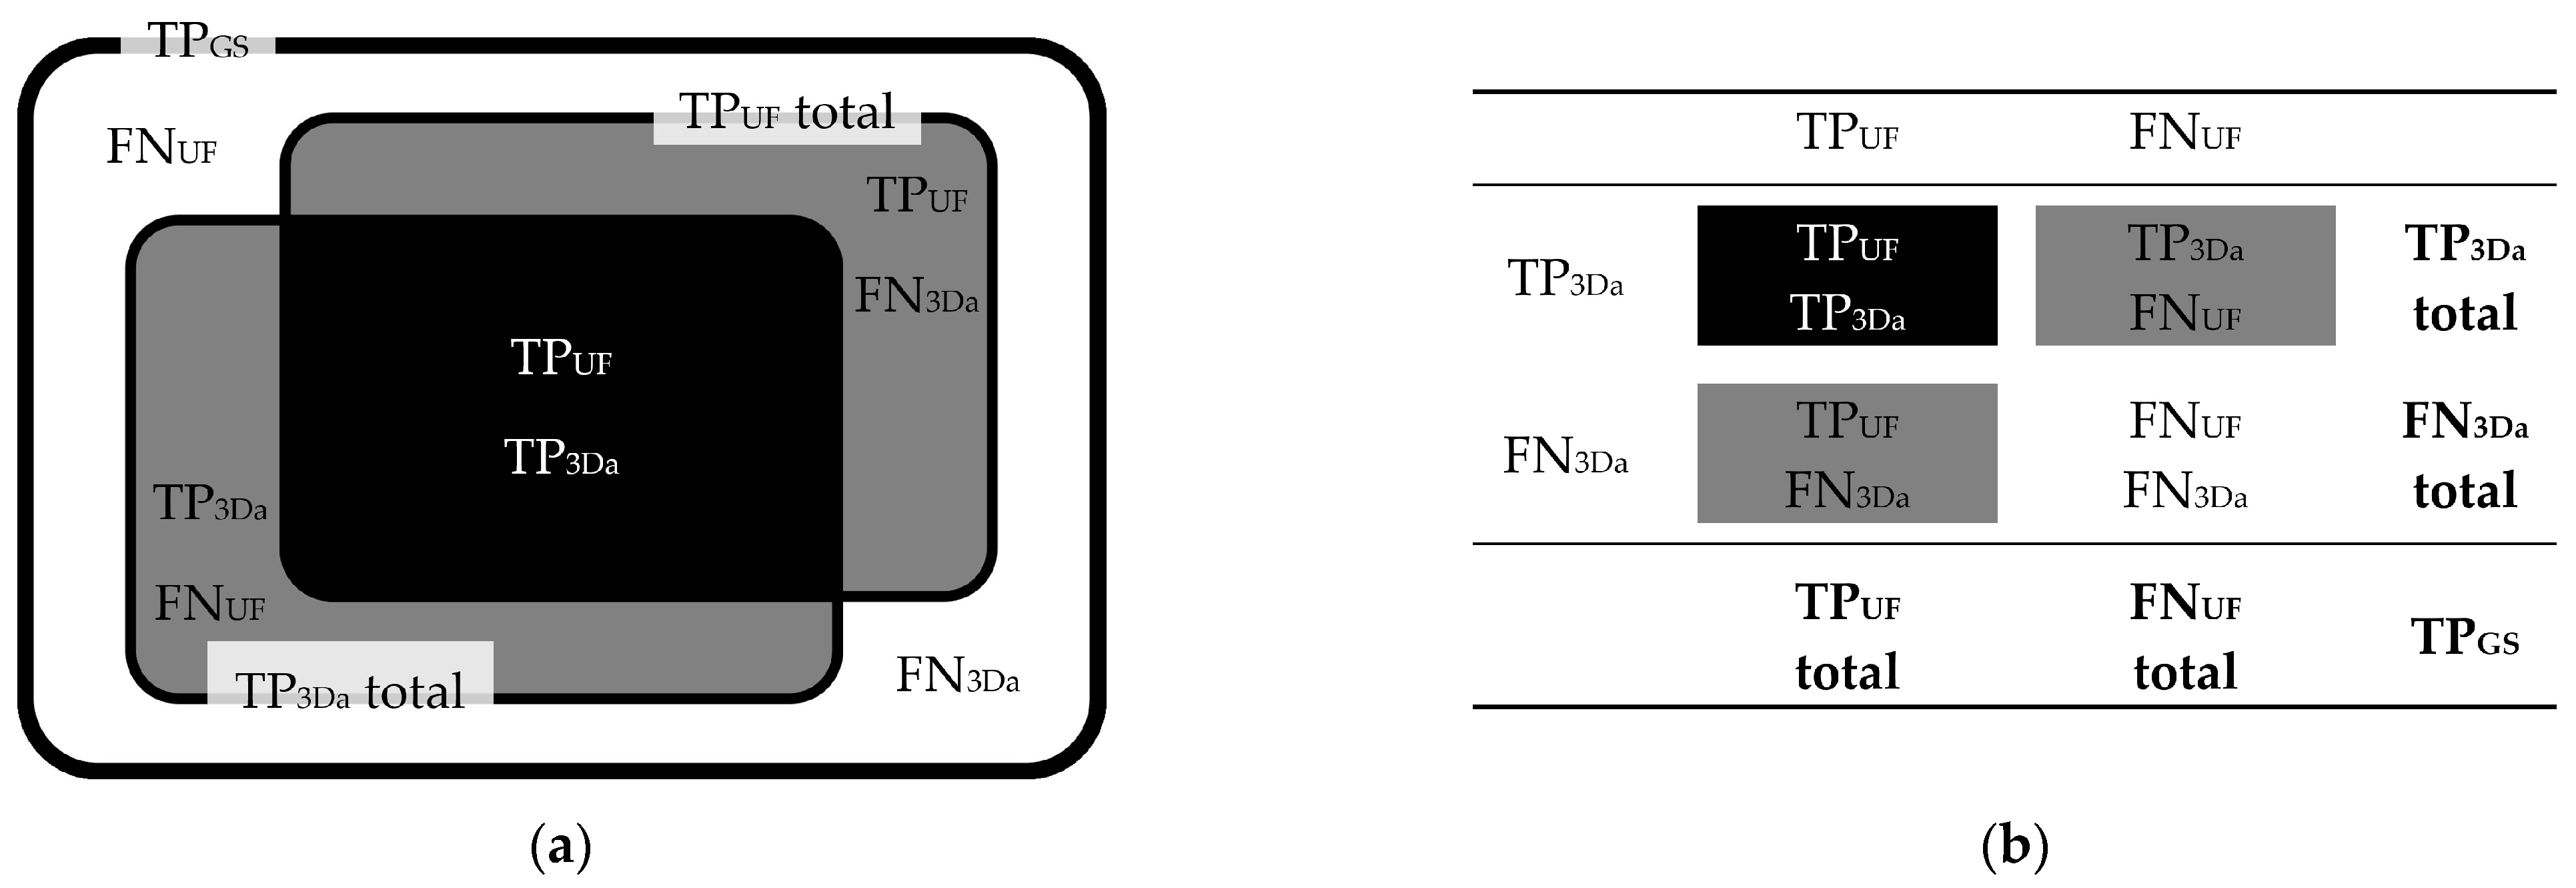

3.2.1. FLAIRUF Compared with FLAIR3Da